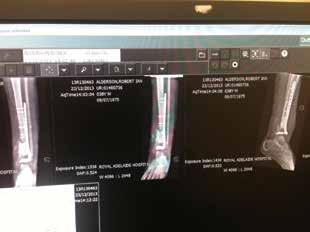

Above: in hospital after surgery in December 2013 wearing a bum bag which contained a balloon (inside a canister) for administering antibiotics; facing page, clockwise from top left: in the old RAH with a gauze dressing over the skin graft in November 2013; the wound in May 2015 after the internal metal work had failed; the wound after gracilis free flap surgery in November 2013; facing page below: Alderson’s left thigh from which surgeons took the skin graft.

Above: Alderson and wife Julie; facing page, top: X-rays which showed the internal reconstruction work in October 2013; below: in hospital the day after his amputation in October 2015.